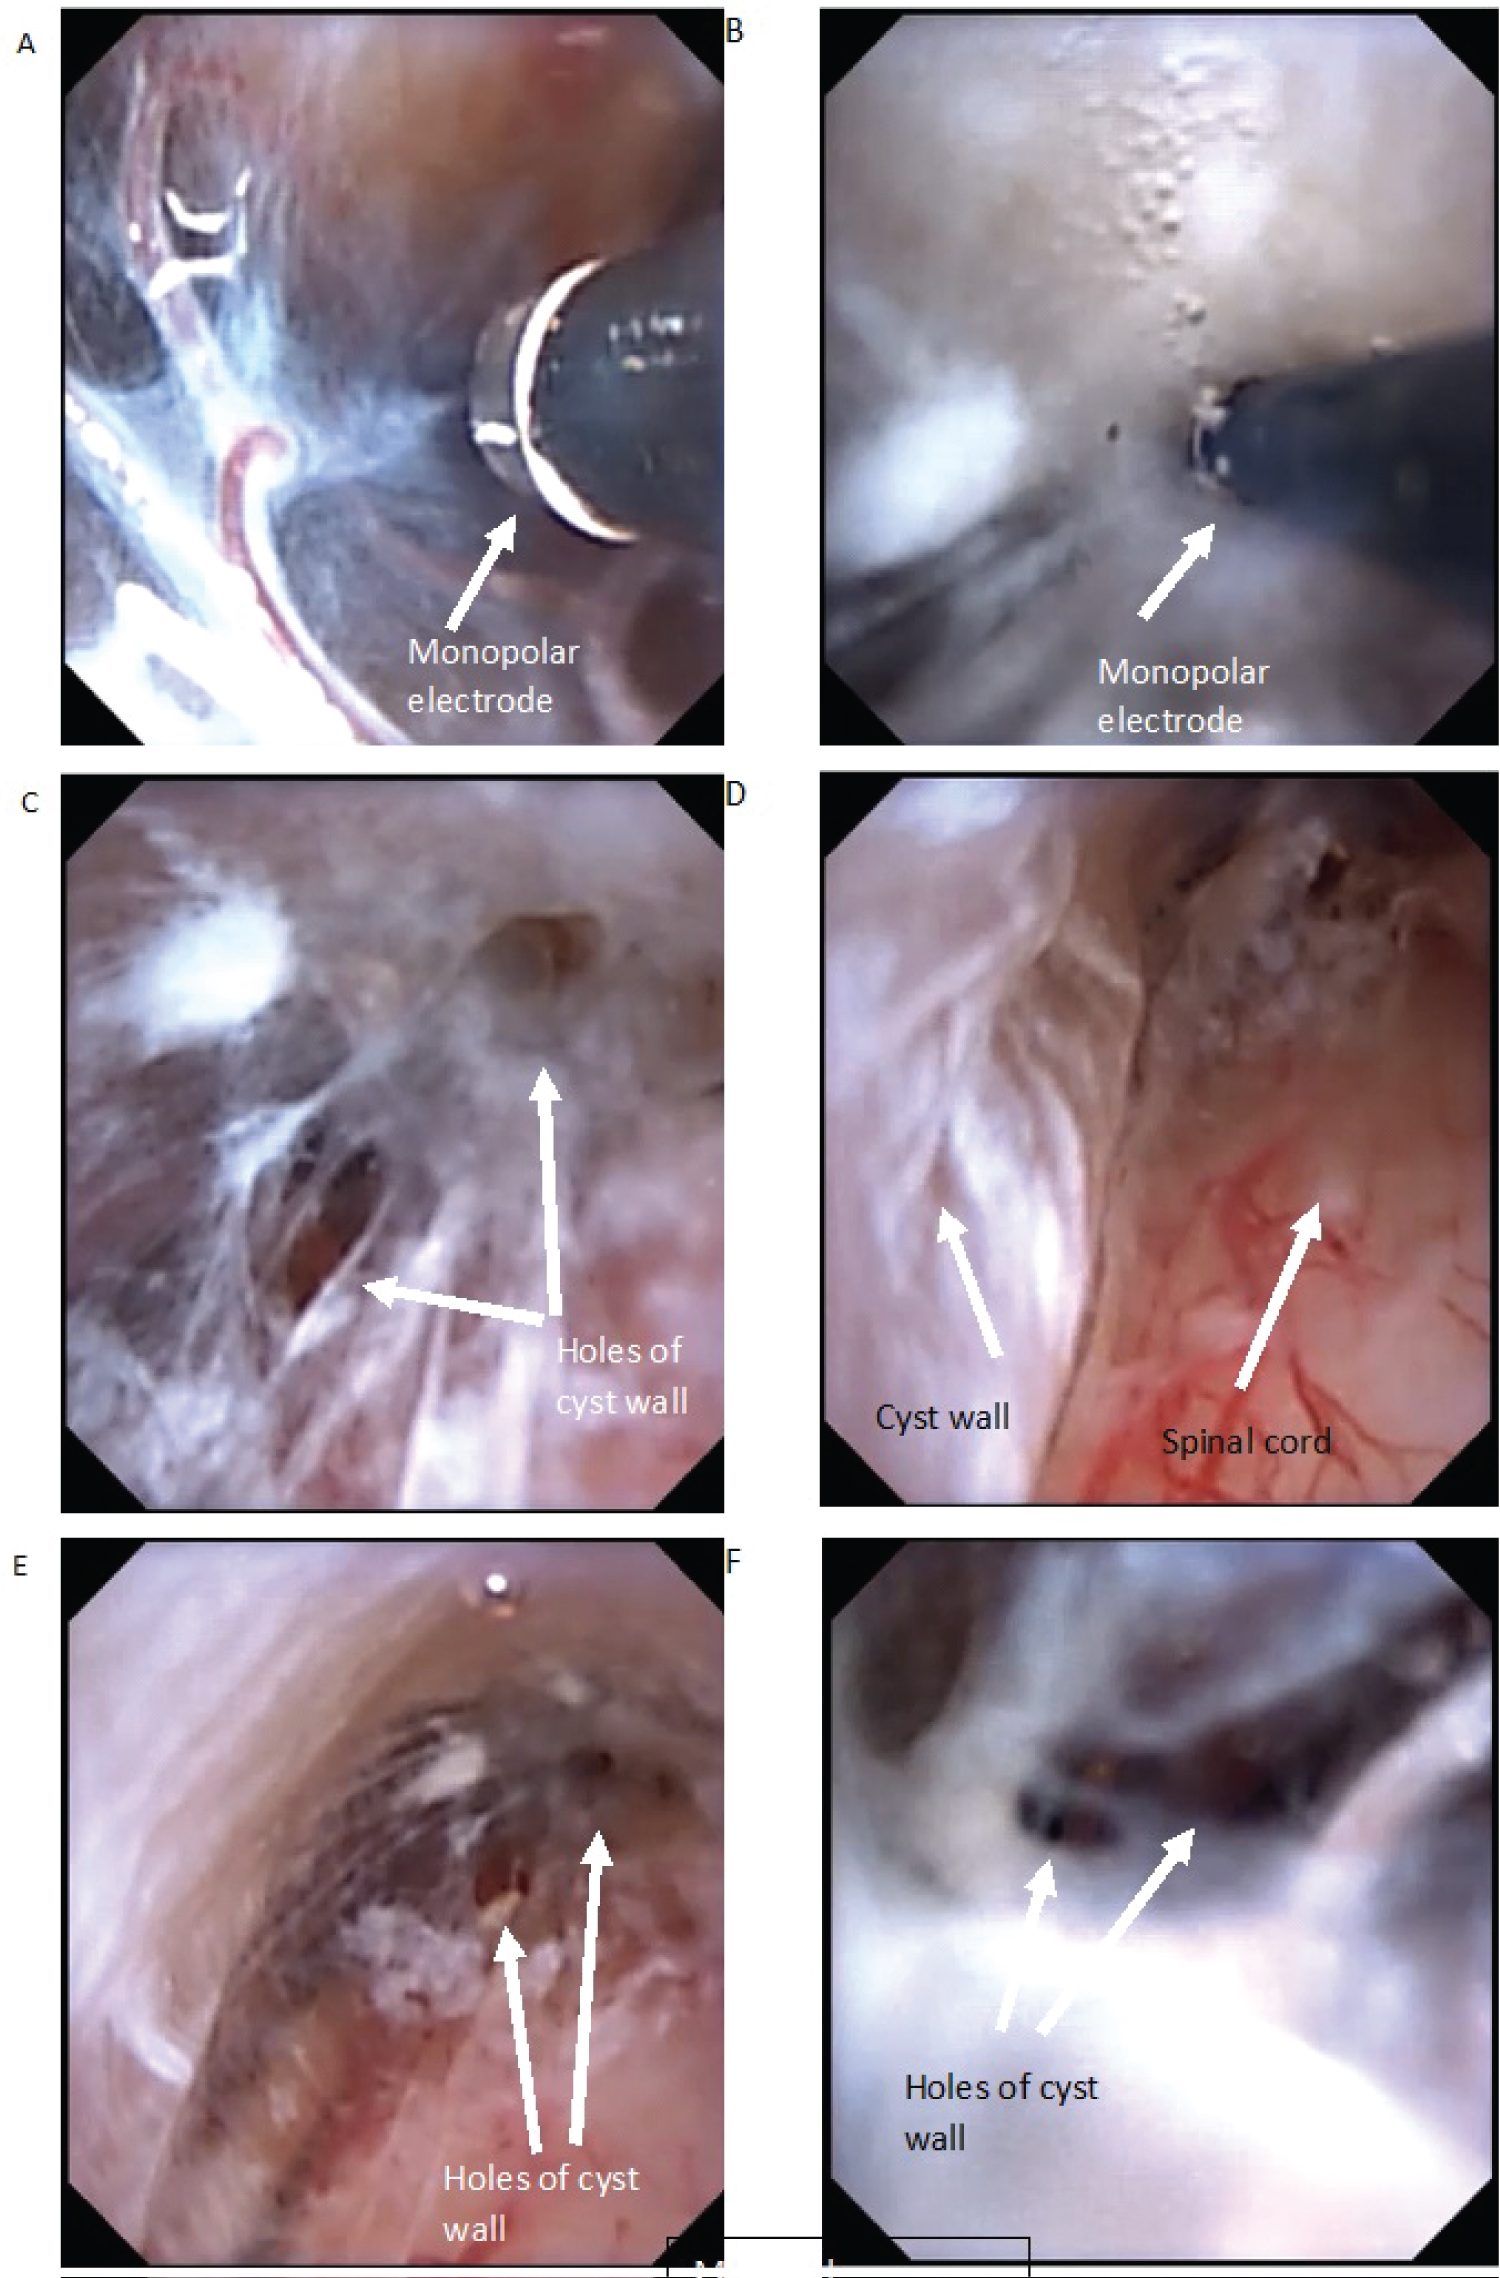

The cavity of the arachnoid cyst was revised - no communication of the cyst with the subarachnoid space was revealed. Perforation of the upper and lower pole of the cyst was made with a monopolar coagulator. Thus, communication of the cyst with the subarachnoid space is achieved (Figure 3).

Figure 3: Intraoperative photo (A) Cranial wall of arachnoid cyst. Monopolar electrode; (B) Cyst wall penetration with monopolar electrode; (C,E,F) Holes after penetration; (D) Dorsal wall of arachnoid cyst and dorsal surface of spinal cord. View Figure 3